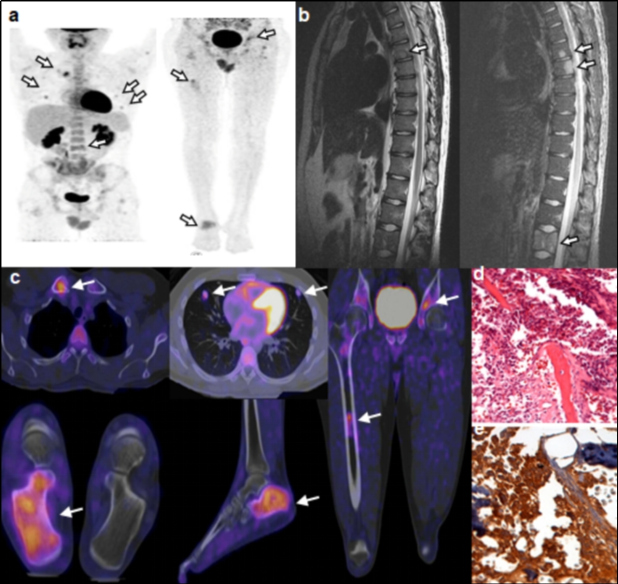

El ID calculado considerando los pacientes con etiología maligna confirmada mediante biopsia o seguimiento, arrojó un valor de 47%. La proporción de FP tomando en cuenta aquellos pacientes con al menos un hallazgo positivo en el PET-CT con otra etiología confirmada que no fuera maligna y aquellos en los cuales no fue posible determinar el tipo de etiología mediante biopsia o seguimiento, fue de 27%. De los pacientes en los que se encontró una etiología maligna, 49 casos fueron confirmados mediante biopsia y 1 mediante seguimiento. De los pacientes con biopsia, el diagnóstico de anatomía patológica más frecuente fue el adenocarcinoma pobremente diferenciado (tabla 1). En cuanto a localización, el sitio primario más común fue el pulmón, seguido del páncreas (tabla 2). Las figuras 1-4 ilustran algunos casos representativos de nuestra serie.